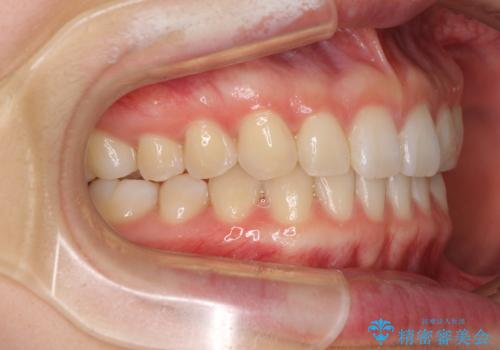

インビザラインによるすきっ歯の改善

- 上の前歯の隙間を気にして来院された患者様です。

インビザラインにより、隙間を閉じながら、隙間の原因であるディープバイトを改善していくこととしました。

下顎の歯列が強く上顎に咬みこむことで隙間ができてしまうため、マウスピースの保定装置では後戻りのリスクが高くなってしまいます。

そのため、上下ともに前歯の裏側を細いワイヤーで固定し、その上から保定装置のマウスピースを使用していただくこととしました。